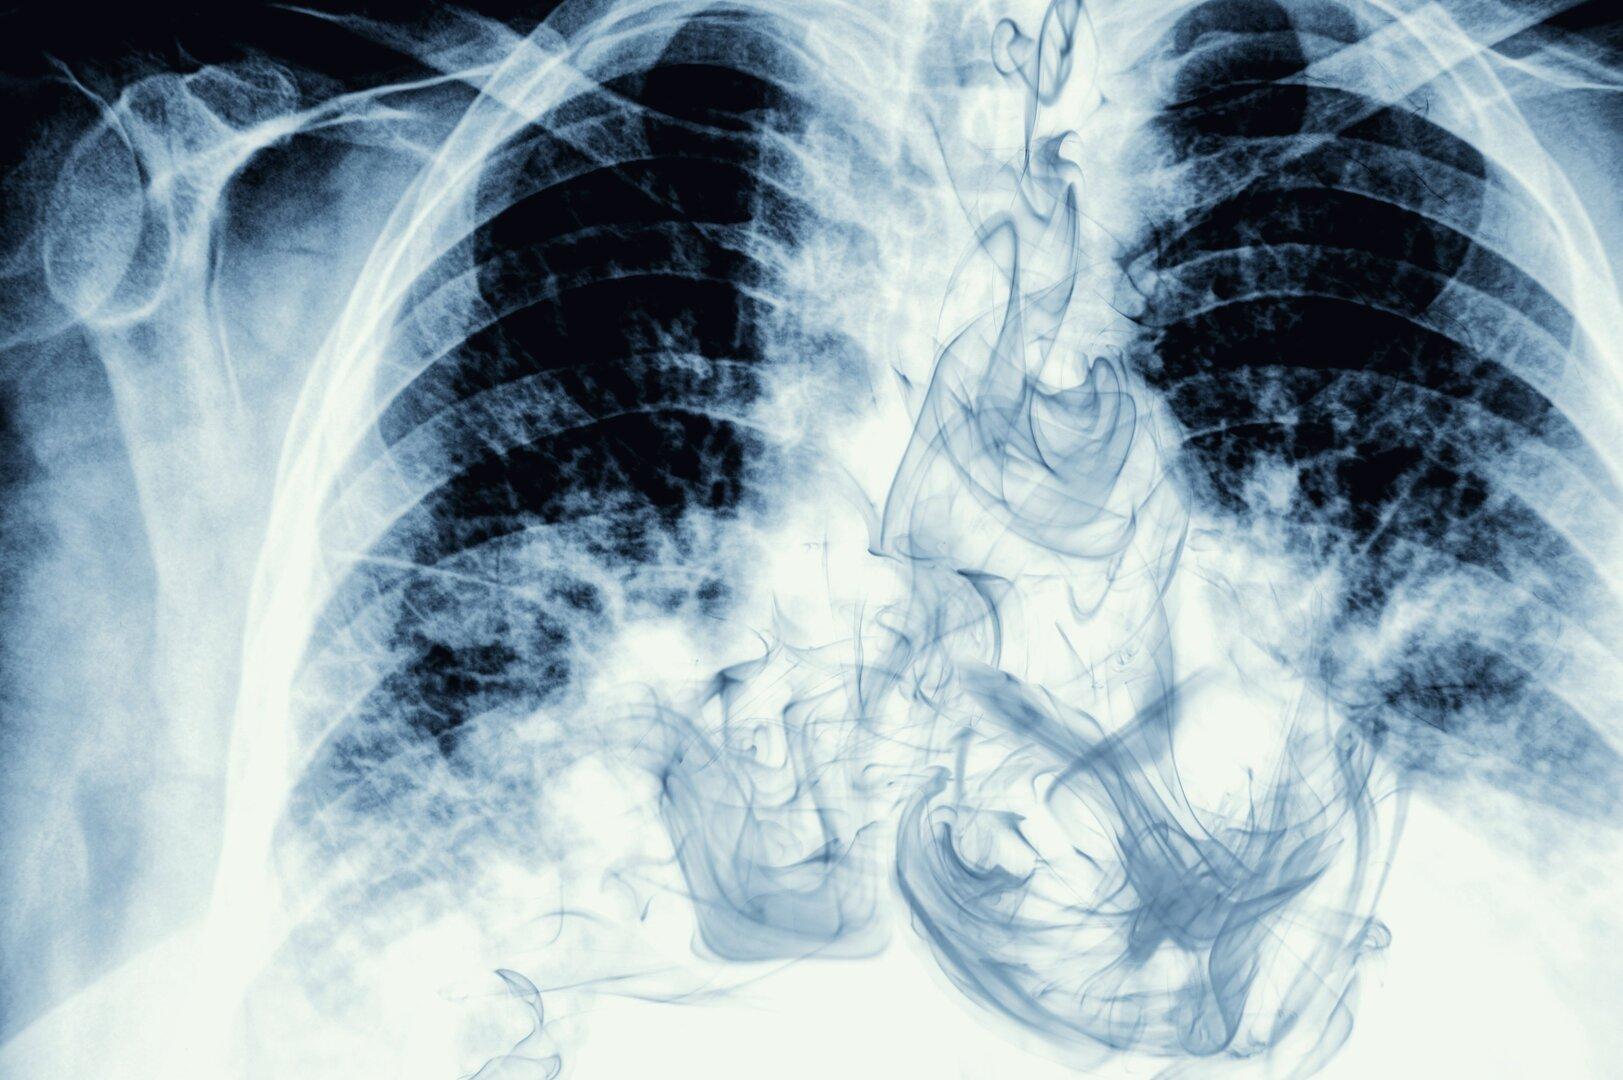

Am 1. April 2026 startet in Deutschland ein bundesweites Lungenkrebs‑Screening für starke Raucherinnen und Raucher zwischen 50 und 75 Jahren. Ziel ist es, mithilfe einer Niedrigdosis‑Computertomographie Tumoren bereits im Frühstadium zu erkennen – und damit die Heilungschancen deutlich zu verbessern. Das Programm gilt als Meilenstein in der Krebsfrüherkennung und basiert auf jahrelanger Vorbereitung, klar definierten Qualitätsstandards und internationalen Studien. In Österreich hingegen warten Risikopersonen noch auf eine vergleichbare Maßnahme. Mit 5.000 Neuerkrankungen pro Jahr und einer Sterblichkeit von jährlich 4.000 Fällen ist Lungenkrebs für rund ein Viertel aller Krebs-Todesfälle verantwortlich. Trotz der hohen Sterblichkeit und überzeugender internationaler Daten, die für ein Screening sprechen,  hat das Screening‑Komitee des Gesundheitsministeriums bisher keine Empfehlung für eine Umsetzung ausgesprochen. Bernd Lamprecht , Vorstand der Universitätsklinik für Innere Medizin 4, Pneumologie, am Kepleruniklinikum in Linz, erklärt, welche Risikogruppen davon profitieren und welche Schritte nötig wären, damit auch Österreich in den kommenden Jahren nachzieht, aber auch warum das Screening kein Freibrief fürs Rauchen sein soll. KURIER: Herr Professor Lamprecht, ab dem 1. April 2026 startet in Deutschland ein bundesweites Lungenkrebs‑Screening für Risikogruppen. Warum ist diese Maßnahme aus Ihrer Sicht so wichtig – und welche Chancen bietet sie? Lamprecht: Wir wissen aus internationalen Daten, dass wir mit einem solchen Programm Leben retten können. Eine Früherkennung von Lungenkrebs mittels Low‑Dose‑CT‑Screening (niedrigere Strahlendosis als bei einer Standarduntersuchung, Anm.) senkt die Sterblichkeit in Risikogruppen signifikant. Technisch ist das möglich. Und wird Lungenkrebs früh erkannt, sind die Behandlungsmöglichkeiten und Heilungschancen deutlich besser. Leider sind aktuell bei Erstdiagnose rund zwei Drittel aller Fälle bereits weit fortgeschritten, und etwa die Hälfte ist sogar schon metastasiert. Wäre es nicht besser auf Prävention zu setzen? Natürlich ist es am besten, Lungenkrebs gar nicht erst entstehen zu lassen – und das gelingt nur, wenn die Risikofaktoren konsequent reduziert werden. Deshalb sollte jedes Früherkennungs‑ oder Screeningprogramm von einer wirksamen Raucherberatung und Raucherentwöhnung begleitet werden. So wird ausgeschlossen, dass der Eindruck entsteht, ein organisiertes Screening sei ein „Freibrief“ fürs Rauchen. Denn wer glaubt, mit den bestehenden Risikofaktoren einfach weiterleben zu können, weil man einmal im Jahr zur Früherkennungsuntersuchung geht, irrt. Das Screening hat seinen größten Nutzen dort, wo das Risiko bereits hoch ist und es darum geht, das „Unausweichliche“ zumindest möglichst früh zu erkennen und wirksam zu behandeln. Langfristig bleibt Prävention jedoch die wichtigste und kosteneffizienteste Maßnahme. Wie lange arbeiten unsere Nachbarn schon an der Umsetzung? In Deutschland wurde im Oktober 2023 ein Positionspapier veröffentlicht, das alle Rahmenbedingungen für ein flächendeckendes Screening beschreibt. Herausgegeben wurde es von drei Fachgesellschaften: der Deutschen Röntgengesellschaft, den deutschen Lungenfachärzten und den deutschen Lungenchirurgen. Darauf basierend hat man die Umsetzung und Finanzierung geplant – jetzt hat das Programm Hand und Fuß. Zwar wird es möglicherweise nicht überall gleichzeitig starten, aber man hat sich grundsätzlich auf ein flächendeckendes Vorgehen geeinigt. Entscheidend ist dabei, die Risikopopulation klar zu definieren. Die da wäre? Das Screening richtet sich an Menschen mit einer langen und intensiven Raucherkarriere . Konkret bedeutet das: mindestens 15 sogenannte „Packungsjahre“ – also beispielsweise eine Packung Zigaretten pro Tag über 15 Jahre – sowie insgesamt mindestens 25 Jahre starken Konsums. Rauchpausen dürfen höchstens zehn Jahre betragen. Anspruch haben sowohl aktive Raucher als auch Ex‑Raucher, die erst seit wenigen Jahren abstinent sind. Zusätzlich sollten auch berufliche Belastungen, etwa durch Staub, Gase und Dämpfe, in die Risikoeinschätzung einbezogen werden. Ein weiterer Risikofaktor, der in Österreich relevant ist, ist die Belastung durch Radon. Radon ist ein natürlich vorkommendes radioaktives Edelgas, das beim Zerfall von Uran im Boden entsteht. Es ist unsichtbar, geruchlos und spielt im Freien keine Rolle, weil es sich dort sofort verflüchtigt. In geschlossenen Räumen jedoch – insbesondere in Gebäuden mit undichter Gebäudehülle – kann es sich in hoher Konzentration ansammeln. Ist Radon ein Risikofaktor für Lungenkrebs? Ja. Langfristige Radonbelastung gilt nachweislich als eine der wichtigsten Ursachen für Lungenkrebs bei Nichtrauchern und kann das Risiko bei Rauchern zusätzlich verstärken. In Österreich leben schätzungsweise rund 500.000 Menschen in Regionen mit relevant erhöhter Radonkonzentration. Das ist aber nur wenig bekannt? Das ist ein spannendes Thema. Das Land Oberösterreich beispielsweise hat dieses Problem erkannt und bietet Sanierungsförderungen an, um undichte Gebäudehüllen zu verbessern und die Radonkonzentration in Innenräumen zu senken. Dazu gehören Maßnahmen wie das Abdichten von Kellern, die Verbesserung der Belüftung und spezielle Radon‑Absaugsysteme. Zurück zum Screening. Wie kommt der Risikopatient zum CT? Auf alle Fälle braucht es jemanden, der Einblick in die Risiko-Population hat. Also etwa der Hausarzt, der seine Patienten kennt und weiß, welche Personen Raucher/Exraucher in der entsprechenden Altersgruppe sind. Auch die Krankenkassen könnten Einblick haben. Der Patient erhält die Empfehlung, und die Untersuchung sollte im niedergelassenen Bereich stattfinden, nicht in Krankenhausambulanzen. Dort müssen Qualitätsstandards eingehalten, moderne Geräte genutzt und eine gewisse Zahl an Untersuchungen pro Jahr durchgeführt werden. Unauffällige Befunde bedeuten: alles bestens. Auffällige Befunde werden an spezialisierte Zentren zur Abklärung weitergeleitet. Gibt es einen konkreten Zeitplan in Österreich? Zuerst braucht es eine entsprechende Empfehlung des Nationalen Screening‑Komitees im Bundesministerium . Dieses muss auf Basis internationaler Daten und Erfahrungen sowie der Umsetzung in anderen europäischen Ländern Maßnahmen priorisieren und befürworten. Danach braucht es klare Umsetzungsbestimmungen: Finanzierung, Zuständigkeiten, Einladungssystem, Durchführung und Befundmanagement. Ehrlich gesagt, es überrascht mich nicht, dass wir nicht die Schnellsten sind – man denke nur an den Nichtraucherschutz in der Gastronomie, wo wir fast europäisches Schlusslicht waren. Also in Sachen Screening, liegt noch einiges an Überzeugungsarbeit vor uns. Wann, schätzen Sie, ist eine Umsetzung in Österreich realistisch? Ich wünsche mir sehr, dass wir es in den nächsten zwei bis drei Jahren auch in Österreich schaffen, ein solches Programm einzuführen. Offen gesagt, fände ich es fast schon unangenehm, wenn wir jetzt noch große Pilotstudien starten würden – wir müssen doch nicht erst in Österreich erforschen, was bereits in halb Europa erfolgreich umgesetzt wird und wofür überzeugende internationale Studiendaten vorliegen. Was wir aber tun könnten, sind gezielte Pilotphasen durchzuführen: zum Beispiel in einer ländlichen Region, einem städtischen Bezirk, einmal im Westen und einmal im Osten des Landes. So könnten wir sehen, wie es funktioniert, wo mögliche Hürden liegen und wie wir diese überwinden. Ganz wichtig ist, dass die Informationen über diese Vorsorgeuntersuchung auch jene Menschen erreichen, die ein besonders hohes Risiko haben – etwa, weil sie überdurchschnittlich viel rauchen oder an staubigen Arbeitsplätzen tätig sind. Und natürlich müssen die nötigen Ressourcen rechtzeitig bereitstehen. Wenn wir die Menschen zur Teilnahme einladen, muss es auch möglich sein, ihnen zeitnah Untersuchungstermine anzubieten. Denn nichts wäre schlechter, als Werbung für eine Maßnahme zu machen und dann keine Termine anbieten zu können. Siehe Herpes Zoster Impfung. Zuerst wurde groß betont, wie wichtig und wirksam sie ist – und dann gab es nicht sofort ausreichend Impfstoff.